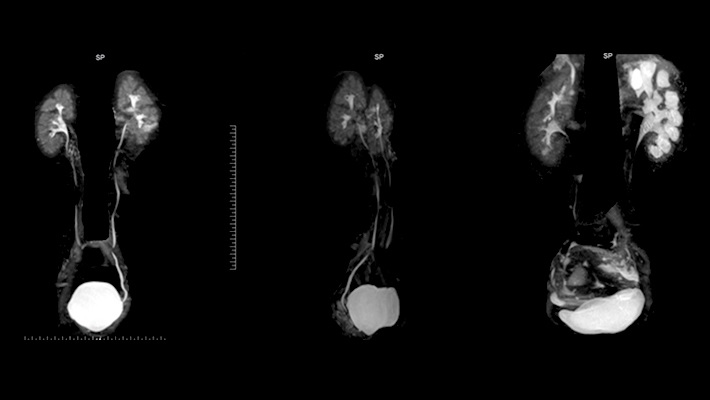

Онлайн-запись на приёмУрография — рентгенологическое исследование, позволяющее оценить строение и проходимость мочевыводящих путей. Исследование может выполняться с контрастом или без него и визуализирует почки, чашечно-лоханочную систему, мочеточники и мочевой пузырь. Метод помогает выявить причины боли в пояснице, появления крови в моче и нарушений мочеиспускания.

- внутривенная (экскреторная) — контраст вводится в вену, фильтруется почками, заполняет чашечки, лоханки, мочеточники и мочевой пузырь, позволяя оценить их проходимость и функциональное состояние;

Пациент опорожняет мочевой пузырь. При контрастной методике препарат на основе йода вводят внутривенно, через катетер в мочевыводящие пути или непосредственно в почку — в зависимости от вида исследования. Затем выполняют серию рентгеновских снимков в заданные интервалы времени. При необходимости делают отсроченные изображения для оценки замедленного оттока мочи.